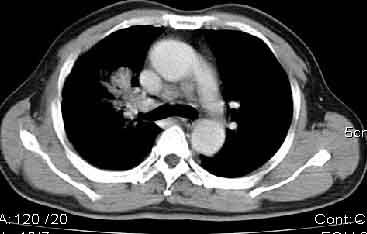

该病例我的诊断意见:右肺上叶周围型肺癌伴纵隔和右肺门淋巴结增大和右肺上叶阻塞性肺炎{病灶周围致密影以近肺门侧明显!}。右侧少量胸腔积液。

一. 1)症状有无发热及慢性过程.2)化验室检查?3)有无tb接触史?二.右肺上叶见片团状影,边界欠清,外侧方见一结节状软组织影,密度欠均匀,内可见低密度坏死区.周围强化明显,肺内见纤维索条影,局部胸膜增厚,但无明确胸膜凹陷.上叶支气管壁增厚,肺门及纵隔淋巴结增大.右侧胸腔少量积液.诊断意见:1右肺上叶慢性感染性疾病(肺tb?)伴肺门,纵隔淋巴结大.右胸少量积液.右肺上叶结节影多为tb球?2右肺上叶周围型肺ca伴肺门,纵隔淋巴结转移待排.右肺上叶炎变(肺门及纵隔淋巴结压迫).右胸少量积液.等待随返结果.